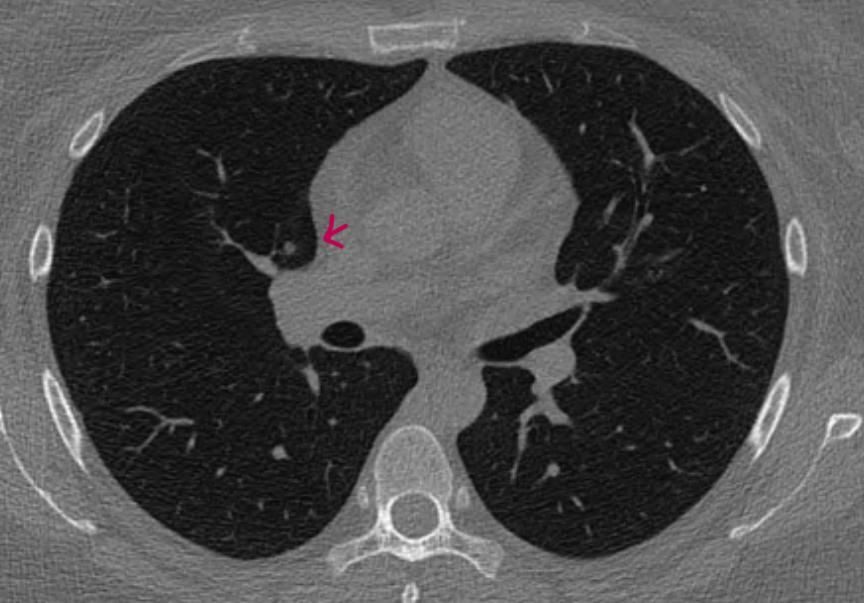

• 3번 째 사진

• 제시된 CT 단면만으로 확정적인 결론을 내리기는 어렵지만, 영상 형태를 종합하면 전형적인 고형 결절로 보기는 제한이 있습니다. 표시된 병변은 경계가 비교적 또렷한 구조처럼 보이지만, 연속된 슬라이스에서 일정한 덩어리로 유지되는 고형 결절의 특징보다는 인접 구조와 이어지는 양상이 의심됩니다. 특히 슬라이스 두께가 1mm와 3mm에서 다르게 보이고 특정 시리즈에서만 강조되는 점은 부분용적 효과에 의해 고형처럼 보일 가능성을 시사합니다.

간유리 결절은 폐 실질 내에서 흐릿하게 음영이 증가하면서 혈관 구조가 그대로 비쳐 보이는 형태가 특징인데, 현재 영상에서는 그러한 전형적인 간유리 음영보다는 비교적 명확한 구조물 형태로 관찰됩니다. 따라서 간유리 결절로 단정하기도 어렵고, 고형 결절로 보기에도 일관성이 부족한 상태입니다.

오히려 폐혈관이 단면으로 보이거나 혈관과 연속된 구조일 가능성이 더 높습니다. 폐 CT에서는 혈관이 단면에서 원형 또는 타원형으로 보일 수 있고, 촬영 각도나 절편 두께에 따라 결절처럼 오인되는 경우가 흔합니다. 동일 위치에서 1년 전과 이후 CT에서 반복적으로 보이는 경우도 정상 혈관 구조로 설명이 가능합니다.

결론적으로 현재 자료만으로는 고형 결절로 확정하기 어렵고, 간유리 결절의 전형적 소견도 아니며, 혈관 또는 혈관 관련 구조일 가능성이 상대적으로 높습니다. 최종 판단은 1mm 이하 얇은 절편의 연속 영상에서 병변이 독립된 결절 형태로 유지되는지, 혈관과 연결되는지를 확인하는 것이 핵심이며 동일 조건의 CT로 비교 판독을 받는 것이 가장 정확합니다.